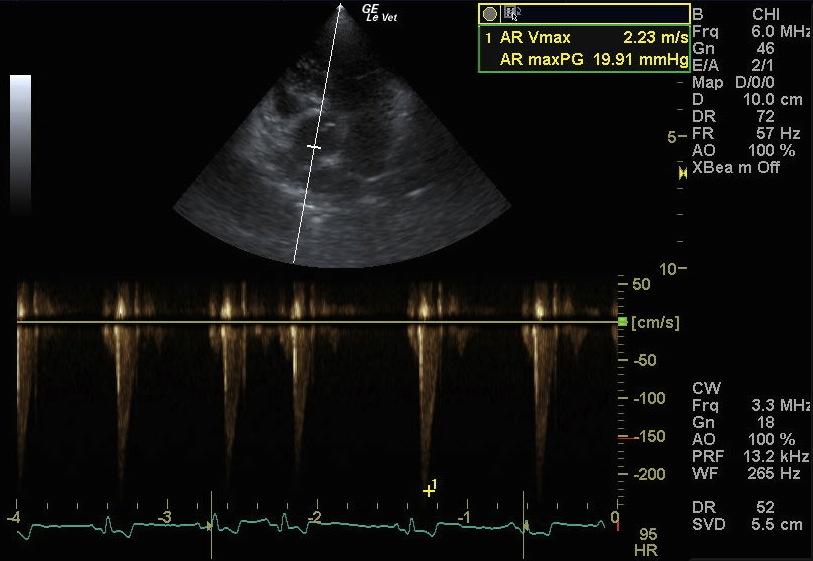

A 9-year-old FS mixed breed dog presented for evaluation of episodic coughing that appeared to be somewhat antibiotic responsive. Survey radiographs showed a normal cardiac silhouette, mild interstitial lung pattern, and an irregular shadow superimposing on the craniobasal cardiac silhouette and adherent to the left thoracic wall from the second to the forth rib. The radiographic changes had been present for almost 2 years.